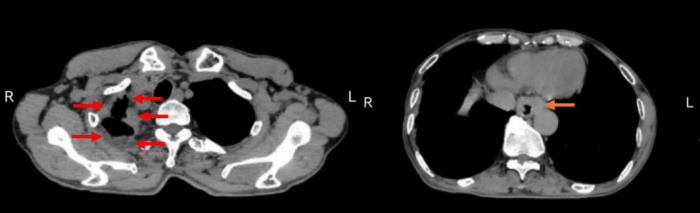

图2 患者既往右侧手术后痕迹,遗留严重粘连(红色箭头),右侧黄色箭头所示为食管癌

胸外科医疗团队经过讨论,为患者制定了个体化的治疗方案,采用腹腔镜辅助下左胸Ivor-Lewis术式为患者进行了食管癌根治术,有效避免了右胸手术史带来的不利影响,术后痰培养还证实患者存在肺部感染和抗生素多重耐药的情况。经过医护团队的精心治疗和护理,患者术后第2天即可下地活动,并在术后一周经造影证实吻合口愈合良好后恢复进食。